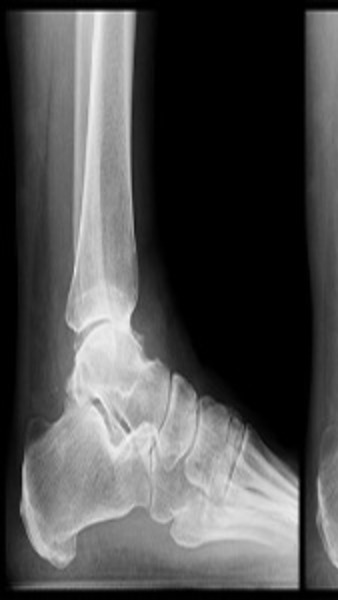

We Provide Best Orthopedic Surgeon in Nagpur